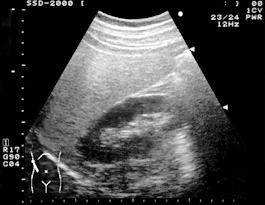

通常脂肪肝は脂肪が貯まるだけでは症状もなく、肝機能に異常は現れませんが、肥満・高脂血症・糖尿病などの生活習慣病を持つ人に多く認められます。脂肪肝になると、超音波検査で肝臓は図のように白く見えるようになります。脂肪肝に加え肝臓に炎症が生じると『脂肪性肝炎』という状態となり、AST/ALT/γGTPなどの肝機能に異常が現れるようになります。脂肪性肝炎の状態が持続すると肝硬変に進展することもあります。ですので脂肪性肝炎の状態となった場合には治療が必要となります。